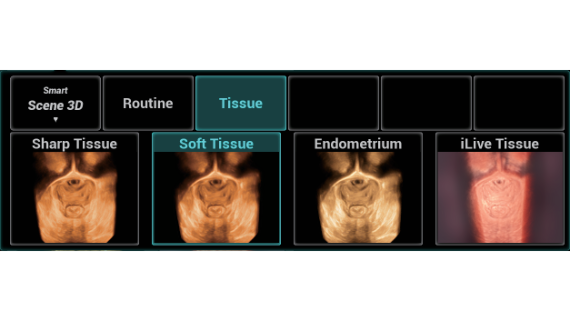

Full-stack Solution Powered by ZST?+

The ZST+ platform is an extraordinary innovation, representing an ultrasound evolution. Transforming ultrasound metrics from conventional beam-forming to channel data based processing. It overcomes the traditional trade-off limitation among spatial resolution, temporal resolution and tissue uniformity, delivering exceptional image quality for infinite imaging solutions with non-stop improvements.